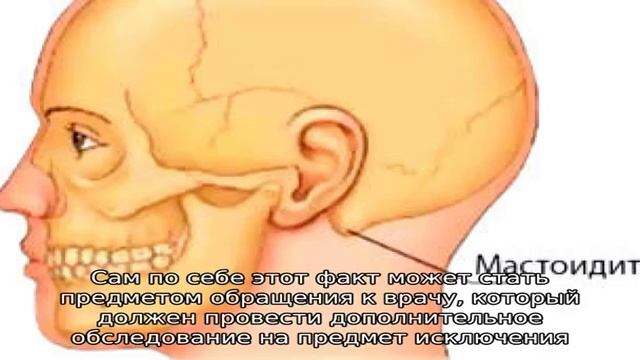

Анатомия сосцевидного отростка